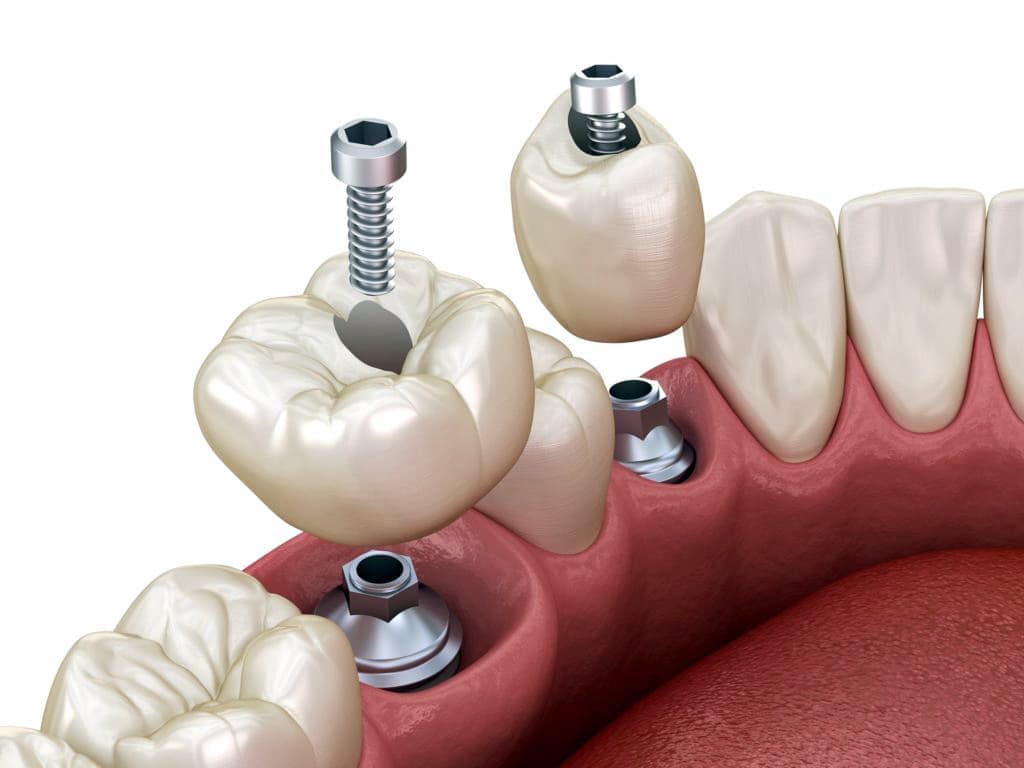

インプラントとは、顎の骨に人工歯根となる金属を埋め込み、それを土台にして、天然の歯と同じような人工の歯を取り付ける治療方法です。